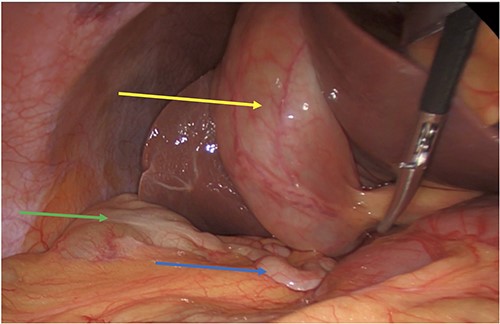

Intraoperatively she had severe inflammation at the Calot’s triangle, and we performed a retrograde, fundus down and cholecystectomy. She was noted to have a subhepatic appendix along with a high riding cecum (Figs 1 and 2). The appendix was not involved in the gallbladder inflammation (Fig. 4).

Acute cholecystitis (yellow arrow) with the high riding cecum (green arrow) and subhepatic appendix (blue arrow).